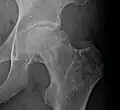

Radiography of total avascular necrosis of right humeral head. Woman of 81 years with diabetes of long evolution. -

Radiography of avascular necrosis of left femoral head. Man of 45 years with AIDS. -

Nuclear magnetic resonance of avascular necrosis of left femoral head. Man of 45 years with AIDS. -